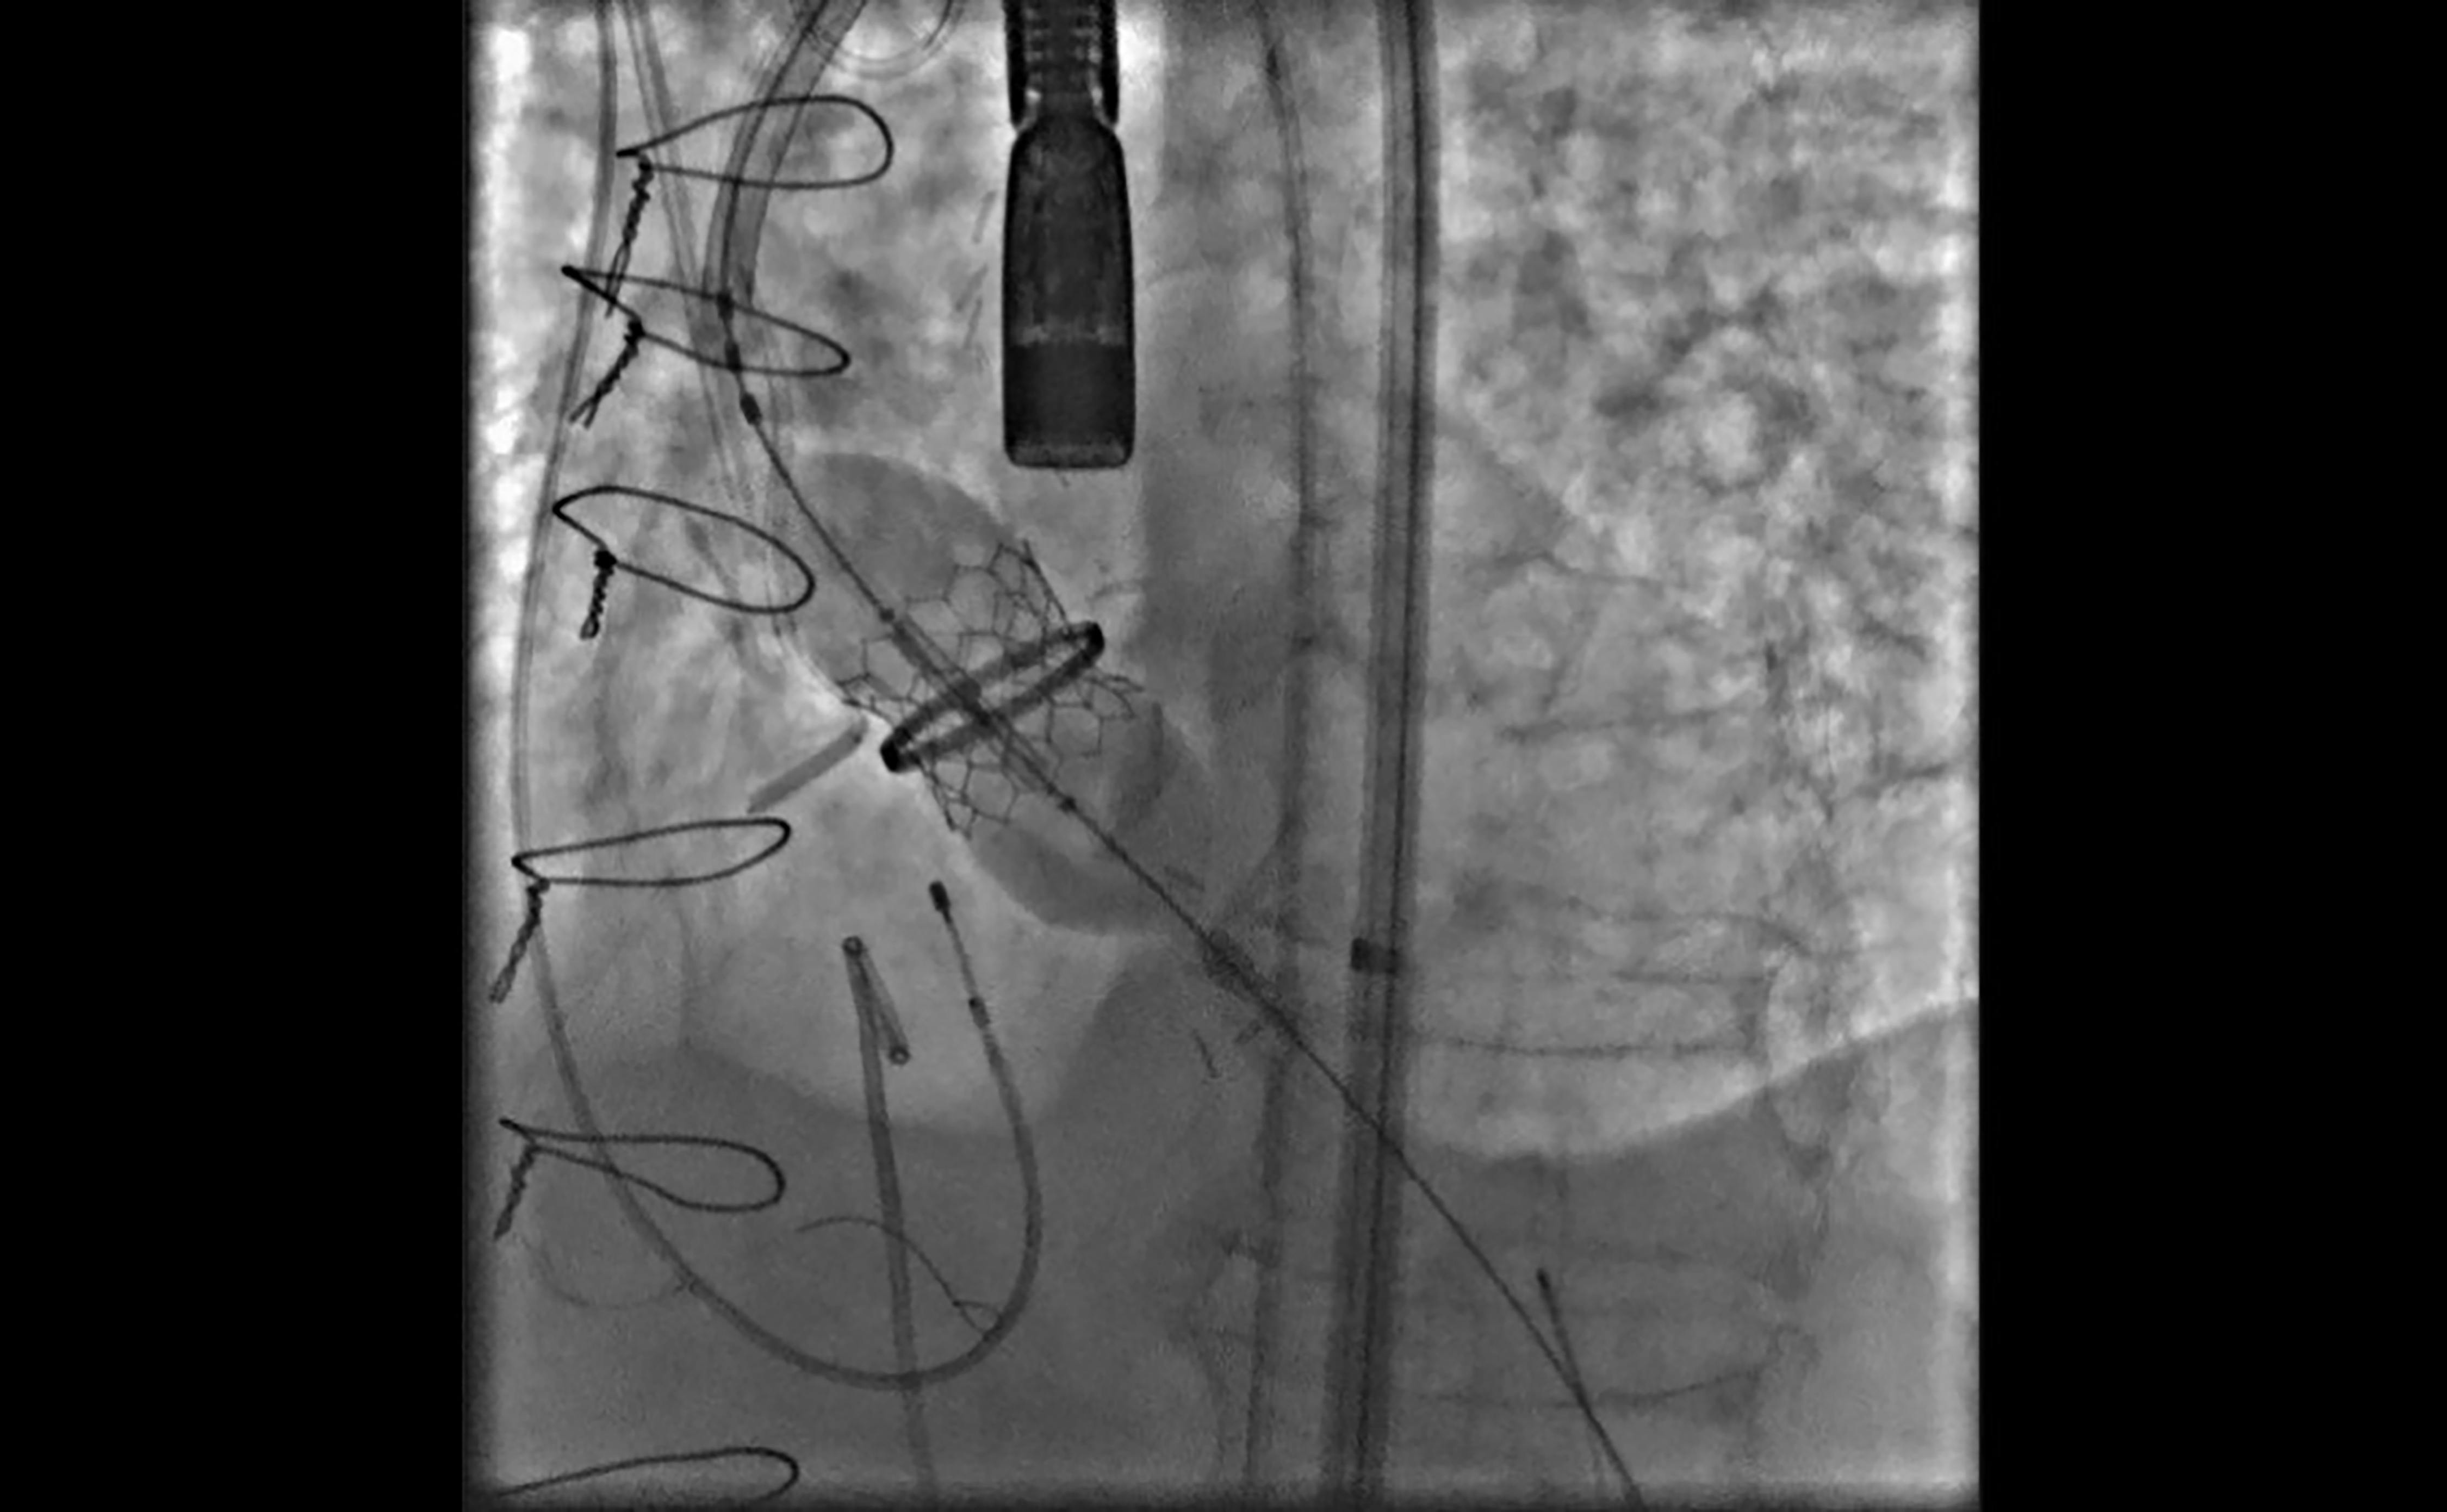

Während des Eingriffs sprengten die Ärzte mit Hilfe eines Ballons am Katheter die eingesetzte mechanische Klappe. Ziel war es, die nicht mehr funktionstüchtigen Flügel in der Klappe auszutauschen. Die Sprengung der alten Klappe prüften die Ärzte zuvor in einem vorklinischen Labortest. Damit keine Fragmente der Karbon-Flügel der „alten“ Klappe in den Kopf gelangen und einen Schlaganfall auslösen konnten, wurden diese mit einem Filtersystem aufgefangen. Am Ende blieb nur der Ring der vormals implantierten Aortenklappenprothese, in den abschließend die neue Herzklappe eingesetzt wurde.

Die neue Klappe wird im Transkatheterverfahren auf den Ring der zurvor gesprengten alten mechanischen Klappe gesetz - ein Durchbruch in der Herzmedizin.